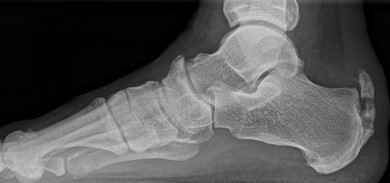

Abbildung 1: Plantarer und dorsaler Sporn im Röntgenbild und im MRT

Abb. 1a und Abb. 1b: großer dorsaler Fersensporn und ein minimaler plantarer Sporn, Patient, 50 Jahre.

Abb. 1c: Bild eines isolierten großen plantaren Fersensporns. Patientin, 32 Jahre.

Dorsaler Fersensporn: Dorsale Fersenschmerzen können auch durch einen echten dorsalen Fersensporn entstehen (siehe Abb. 1). Dieser entsteht als knöcherne Ausziehung durch Verkalkung der Achillessehne an ihrem Ansatz.